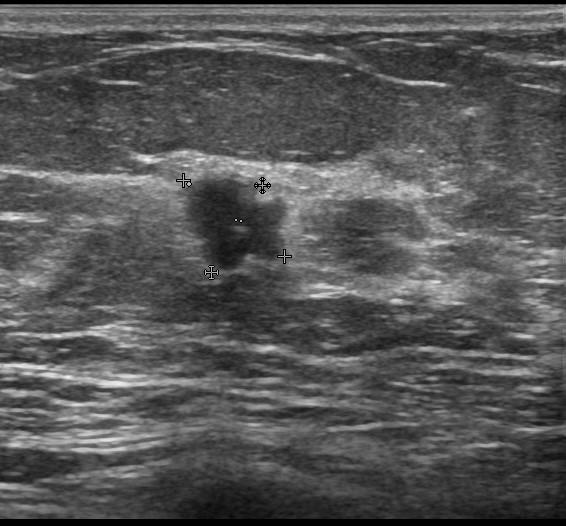

Рис.7 Эхограмма участка аденоза молочной железы

Серошкальный В-режим, с помощью которого врач видит строение вашей молочной железы и может выявить патологические изменения, оценить форму, контур и структуру образования.